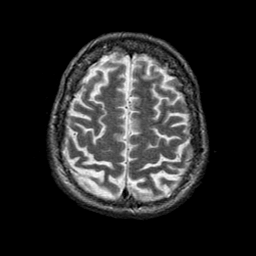

Alzheimer's disease: overlay -- Slice #20

[Home][Help][Clinical] Slice 20